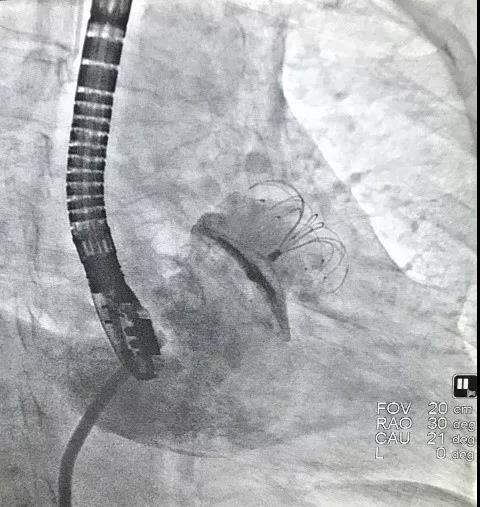

6月3日上午8点,由复旦大学附属中山医院向大会现场直播了一台选用LAmbre™左心耳封堵器系统进行的封堵手术。本例手术由复旦大学附属中山医院的周达新教授和来自香港的林逸贤教授共同完成。接受手术的患者为一名77岁男性,患者3个月前脑梗,并拒绝长期抗凝药物治疗,被诊断为心房颤动,入院评估CHA2DS2-VASc评分为5分。术中造影测量显示其左心耳开口直径为39.9mm,左心耳形态为风向标型。周达新教授和林逸贤教授决定选用型号为LT-LAA-3640的LAmbre™左心耳封堵器对患者实施封堵。手术进行的非常顺利,术后造影显示,患者左心耳封堵完全,无残余分流。

(术后造影)